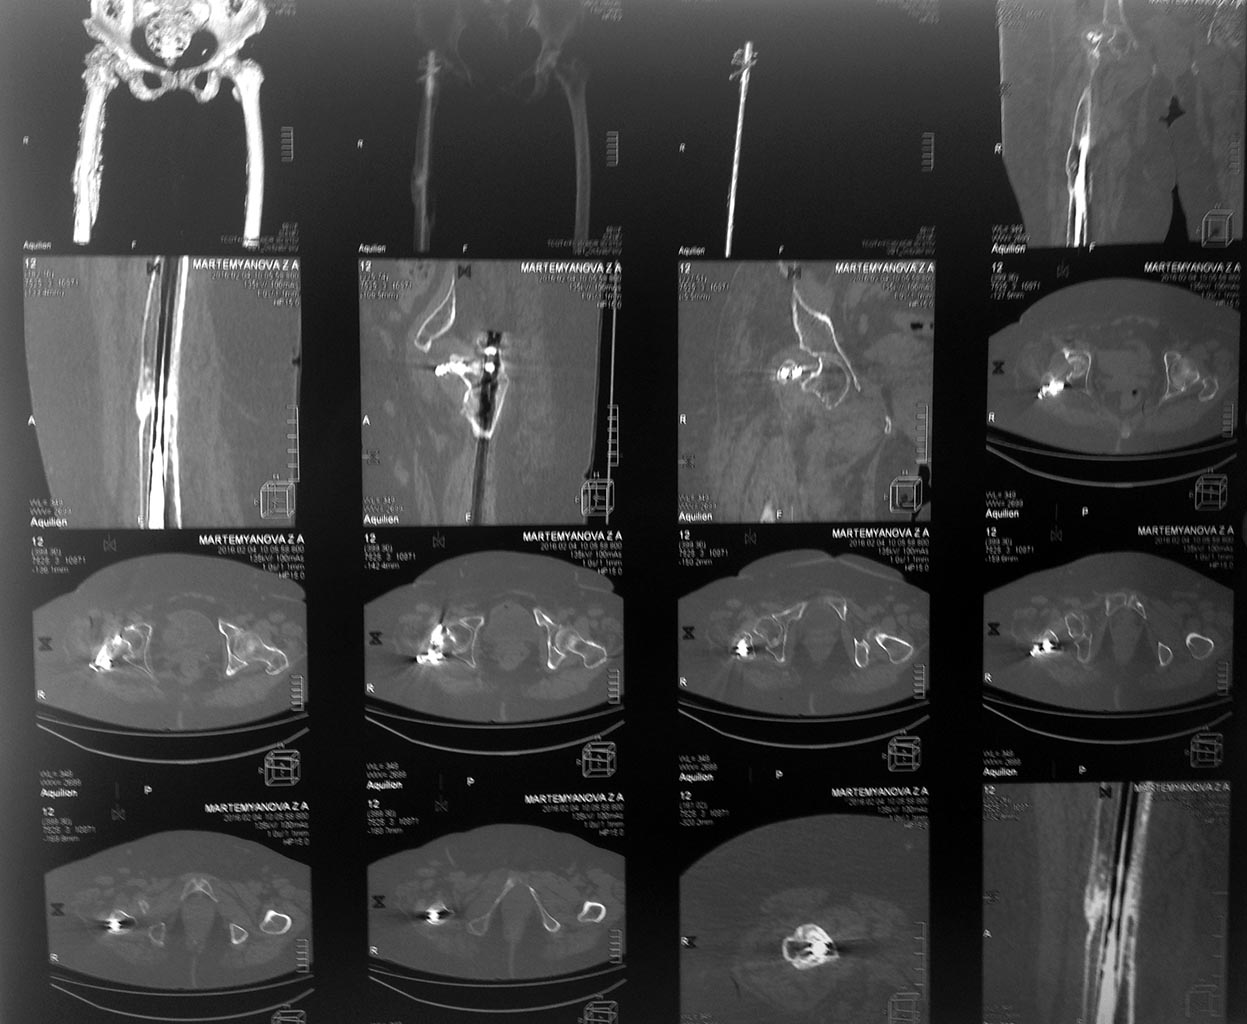

здравствуйте уважаемые коллеги. нужна помощь в дальнейшей тактике по пациентке 62 года вес около 90 кг . передвигается при помощи костылей .

В 2011 году остеосинтез правого бедра на данный момент ложный сустав шейки правого бедра. что бы отправить на ВМП нужно удалить металл, боимся за диафиз бедра. как поступить и кто сможет помочь?

Реостеосинтез ретроградным стержнем. Снимков мало.

Действительно, и ждать, пока окрепнет в области диафиза, можно годами. И если заранее удалять - может ослабленный диатез сломаться, и в условиях болтающегося диафиза уже никто ни на какую ВМП не поедет.

Поэтому оптимально заранее договориться с тем центром, куда пациент поедет для замены сустава, чтобы сделали в одну сессию. И обеспечить коллегам заранее всю информацию - что за железка, и где взять инструмент для удаления.

И для планирования, конечно, этого одного снимка мало - надо все бедро видеть, и зону бывшего перелома особенно хорошо. То ли там схватилось, то ли надо сразу планировать длинную ревизионную ножку, чтобы перекрыть эту зону.

еще снимки

Мозоль достаточно мощная, не должно быть никаких проблем после удаления.

Оптимальный вариант - все сделать в одну операцию. Но если это невозможно организационно, можно удалить стержень. Пациентка ходит на костылях - полной нагрузки не будет из-за ложного сустава шейки. Если после эндопротезирования возникнет подвижность на уровне диафиза - остеосинтез пластиной и костная пластика. Если подвижность возникнет сразу после удаления стержня - все сделать в обратной последовательности (пластина, костная пластика, протез). Безусловно, наличие ревизионной ножки расширило бы возмозможности решения проблемы.

Что с коленным суставом? Судя по снимкам, можно предположить наличие гонартроза. Если это так, то абсолютно беспроигрышным вариантом представляется тотальное интрамедулярное замещение бедренной кости, гвоздь удаляется в эту же сессию. Имеем три в одном: искусственный тазобедренный сустав, искусственный коленный, риск перипротезного перелома исключён. Конечно вопрос бюджета